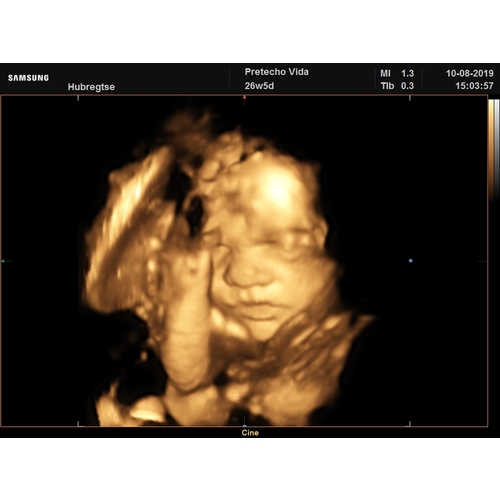

ik had hem met 26.5 weken... heel bijzonder🥰

heb hem in arnhem bij vida laten d0en... zoown lief vrouwtje... had mijn geslachtsbepaling ook bij haar laten doen..😊